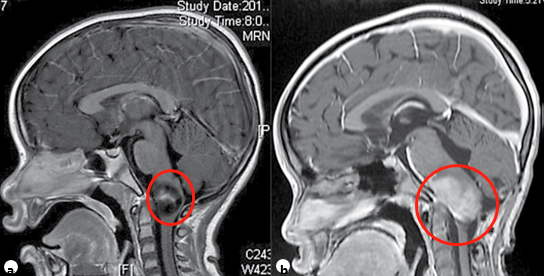

●儿童颈髓胶质瘤典型表现为进行性共济失调、下颅神经功能障碍。神经外科切除术在患者管理中起着重要作用,但应在较高精度的显微神经外科手术设备和持续的术中神经生理学监测条件下进行,目的是达到较大限度的顺利切除病变。许多患者将需要术后化疗和/或FRT(图2)。此外,随着时间的推移,患有此类肿瘤的儿童可能需要某种形式的枕颈稳定。

图2。一名7岁儿童浸润性颈髓肿瘤的矢状面造影后t1加权MRI(a)。活检和组织病理学诊断为低级别肿瘤,尽管使用化疗(b)和FRT来治疗控制肿瘤生长,但肿瘤仍在进展。